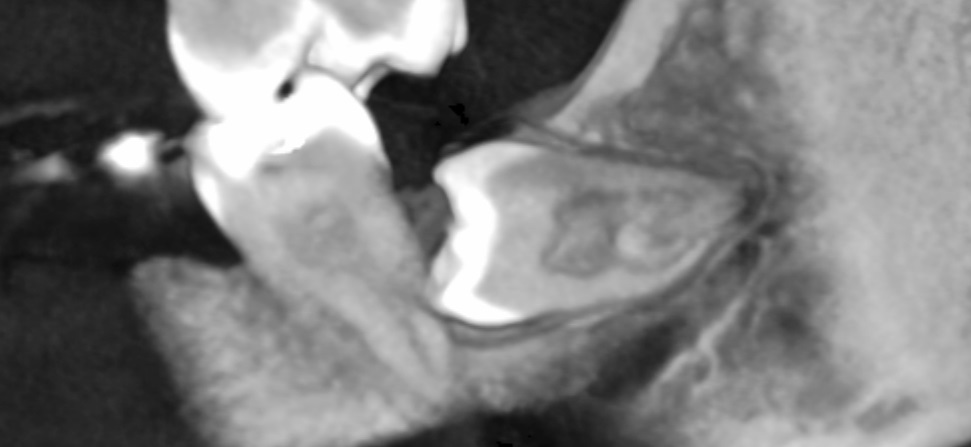

Unter der operativen Weisheitszahnentfernung versteht man die Entfernung der hintersten Zähne der Zahnreihen. Diese ist abzugrenzen von den normalen Weisheitszahnentfernung die zwar ebenfalls ambulant und unter lokaler Anästhesie erfolgen, wobei jedoch es zu keiner chirurgischen Aufklappung kommt.

Gründe für die Entfernung dieser Weisheitszähne können unter anderem am häufigsten Dentiti odifficilis (ein erschwerter Zahndurchbruch), verlagerte Positionen als auch die aus kieferorthopädischer Notwendigkeit der Entfernung sein.